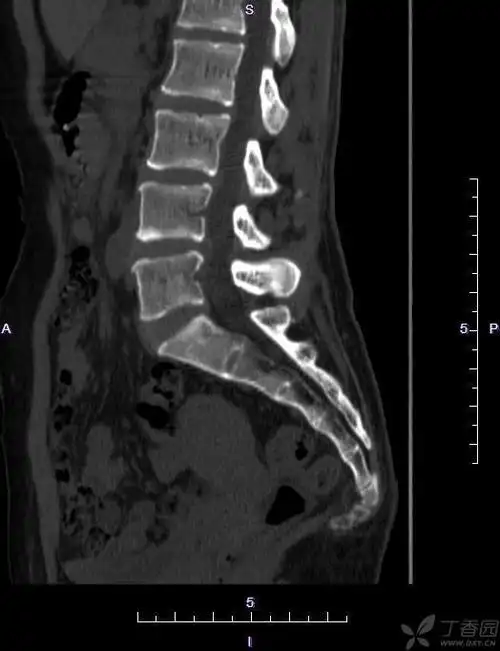

【读片】骶尾椎ct [病例帖]